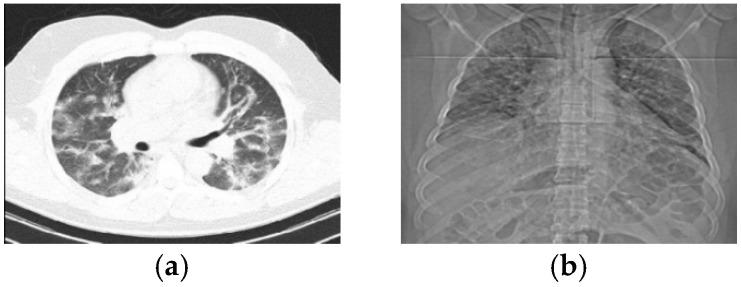

Background: The COVID-19 pandemic has claimed thousands of lives worldwide. While infection rates have declined in recent years, emerging variants remain a deadly threat. Accurate diagnosis is critical to curbing transmission and improving treatment outcomes. However, the similarity of COVID-19 symptoms to those of the common cold and flu has spurred the development of automated diagnostic methods, particularly through lung computed-tomography (CT) scan analysis.

Methodology: This paper proposes a novel deep learning-based approach for detecting diverse COVID-19 variants using advanced textural feature extraction. The framework employs a dual-channel convolutional neural network (CNN), where one channel processes texture-based features and the other analyzes spatial information. Unlike existing methods, our model dynamically learns textural patterns during training, eliminating reliance on predefined features. A modified local binary pattern (LBP) technique extracts texture data in matrix form, while the CNN's adaptable internal architecture optimizes the balance between accuracy and computational efficiency. To enhance performance, hyperparameters are fine-tuned using the Adam optimizer and focal loss function.